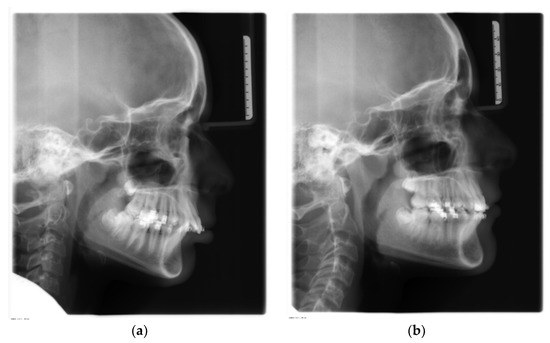

- SNA (°): angle between sella, nasion, and subspinale point A. It indicates the antero-posterior position of the maxilla relative to anterior cranial base (Figure 1, 1);

- SNB (°): angle between sella, nasion, and supramentale point B. It indicates the antero-posterior position of the mandible to anterior cranial base (Figure 1, 2);

- ANB (°): angle resulting from the difference between the SNA and SNB angles, which provide an indication of the sagittal skeletal relationships (Figure 1, 3);

- Wits (mm): is the measure of the segment Ao-Bo where Ao and Bo indicate respectively the projection of point A and point B on the occlusal plane (Figure 2, a);

- SN-Occlusal Plane (°): angle between the cranial base (SN) and the occlusal plane (Figure 1, 4);

- SN-Palatal Plane (°): angle between the cranial base (SN) and the palatal plane (Figure 1, 5);

- SN-Mandibular Plane (°): angle between the cranial base (SN) and the mandibular plane (Figure 1, 6);

- Palatal Plane-Mandibular Plane (°): angle between the bispinal plane and the mandibular plane, expressing intermaxillary divergence (Figure 1, 7);

- Co-Gn (mm): distance from condylion to anatomic gnathion, expressing total mandibular length (Figure 2, b);

- Co-Go (mm): distance from condylion to gonion, expressing the height of the mandibular ramus (Figure 2, c);

- Co-Go-Me (°): mandibular angle (Figure 1, 8);

- Overjet (mm): parameter indicating the measurement of the distance in the sagittal plane between the incisal margin of the upper incisors and the vestibular surface of the lower incisors (Figure 2, d);

- Overbite (mm): distance in the vertical plane between the incisal margin of the upper and lower central incisors (Figure 2, e);

- Molar relationship (mm): distance between the projections in the occlusal plane of the point of contact between the first permanent molars and the adjacent mesial tooth (second deciduous molar or second premolar) (Figure 2, f);

- Inc. Sup.-Pal. Pl. (°): angle expressing the inclination of the axis of the upper central incisor relative to the palatal plane (Figure 1, 9);

- Inc. Inf.-Mand. Pl. (°): angle expressing the inclination of the axis of the lower central incisor relative to the mandibular plane (Figure 1, 10);